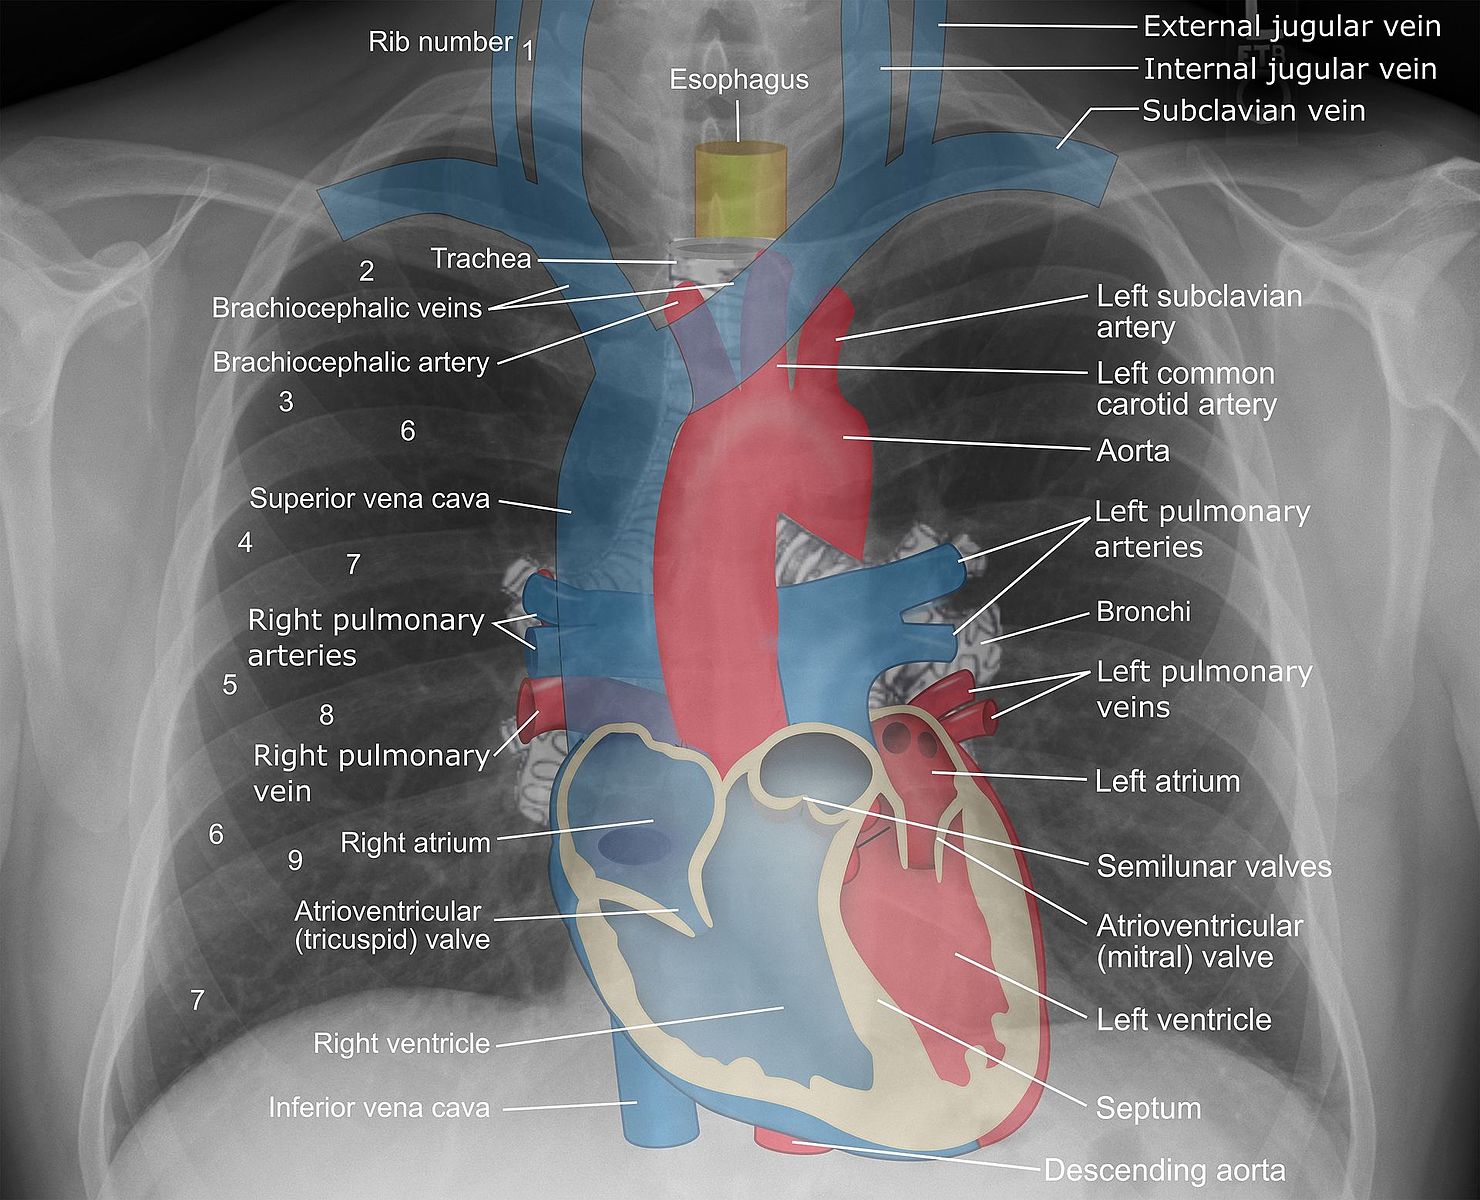

The plain film x ray is the most common radiological diagnostic tool used today. The three main principles when using x rays include: the ability to create electromagnetic radiation at the required wavelength, the ability to focus the radiation onto specific areas and finally the ability of the radiation to be detected once it has travelled through the patient.

X rays can be absorbed in different ways depending on the nature of the tissue. High density tissue like bone will absorb the x rays more and therefore will appear white on an x ray. Low density tissue like organs such as the lungs will not absorb many x rays and hence will appear black on the x ray.